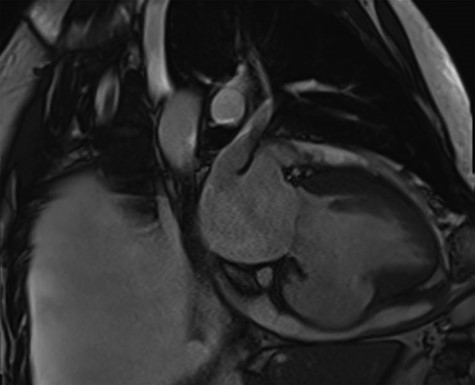

Cardiac MRI described a large aneurysm involving the basal and mid-inferoseptum and extending into the basal and mid-inferior walls (Fig. 2). There was full thickness infarction of the aneurysmal wall and an associated complex VSD with significant left to right flow (Qp:Qs 2.8:1). Coronary angiogram showed a mild circumflex disease and a significant disease of the left anterior descending (LAD) and right coronary artery (RCA) (Fig. 3).

Cardiac MRI demonstrating a LV aneurysm leading to abnormal dilatation of the mitral annulus.